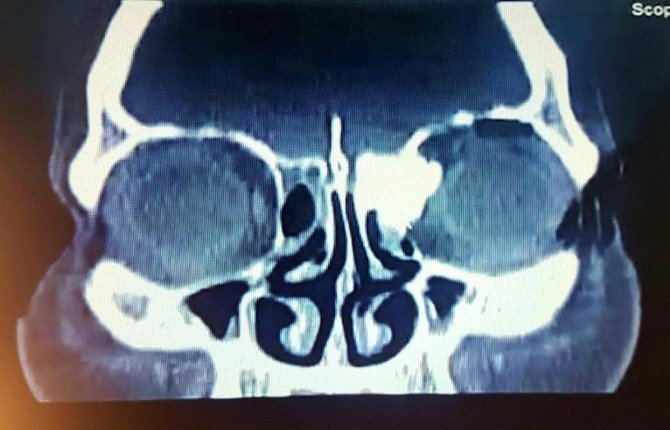

Konuyla ilgili bir açıklama yapan Mehmet Akif İnan Eğitim ve Araştırma Hastanesi K.B.B. Uzmanı Op. Dr. Ahmet Doblan, "Bulanık görme, çift görme ve baş ağrısı şikayetiyle hastanemiz K.B.B. kliniğine müracaat etmiş olan 36 yaşında Bedriye Uysal isimli hastada, yapılan muayene ve tetkikler sonucunda sol etmoid kemikten kaynaklanan ve yaklaşık 1 buçuk santim orbita içerisine uzanan ve orbitada itilmeye sebep olan kitlenin kafa tabanında ön kafa çukuruna da yaklaşık 1 santim kadar girdiği ve beyine doğru uzandığı görüldü. İntraorbital ve intrakranial uzanım gösteren etmoid osteom (kemik tümörü) teşhisi konulan hastaya endoskopik kafa tabanı ve orbita tümörü eksizyonu yapılması gerektiği, ameliyat olmaması durumunda körlük ve beyin zarlarında iltihaplanmaya bağlı menenjit riskinin olduğu anlatıldı.

Hastaya uygulanan medikal tedavinin ardından ameliyata hazır hale gelince yaklaşık 6 saat süren bir operasyonla sadece burun içerisinden girilerek tümör tamamen çıkartıldı. Bu ameliyat devlet hastanelerinde çok nadir olarak yapılan ve genellikle beyin cerrahi göz doktorlarının katılımıyla yüzde ve kafa derisinde kesilerle yapılan bir ameliyattır. Ancak biz burada bunu hiçbir kesi yapmadan baştan sona sadece endoskopik görüntülemeyle gerçekleştirerek ameliyattan sonra yoğun bakım ihtiyacı duymadan hastamızı servise çıkartmayı başardık. Ameliyat sonrası birinci günde çekilen görüntüleme tetkiklerinde hiçbir sorun olmadığı ve tümörün tamamen çıkartıldığı görülen hastanın tamponları alınıp hasta taburcu edildi" dedi.